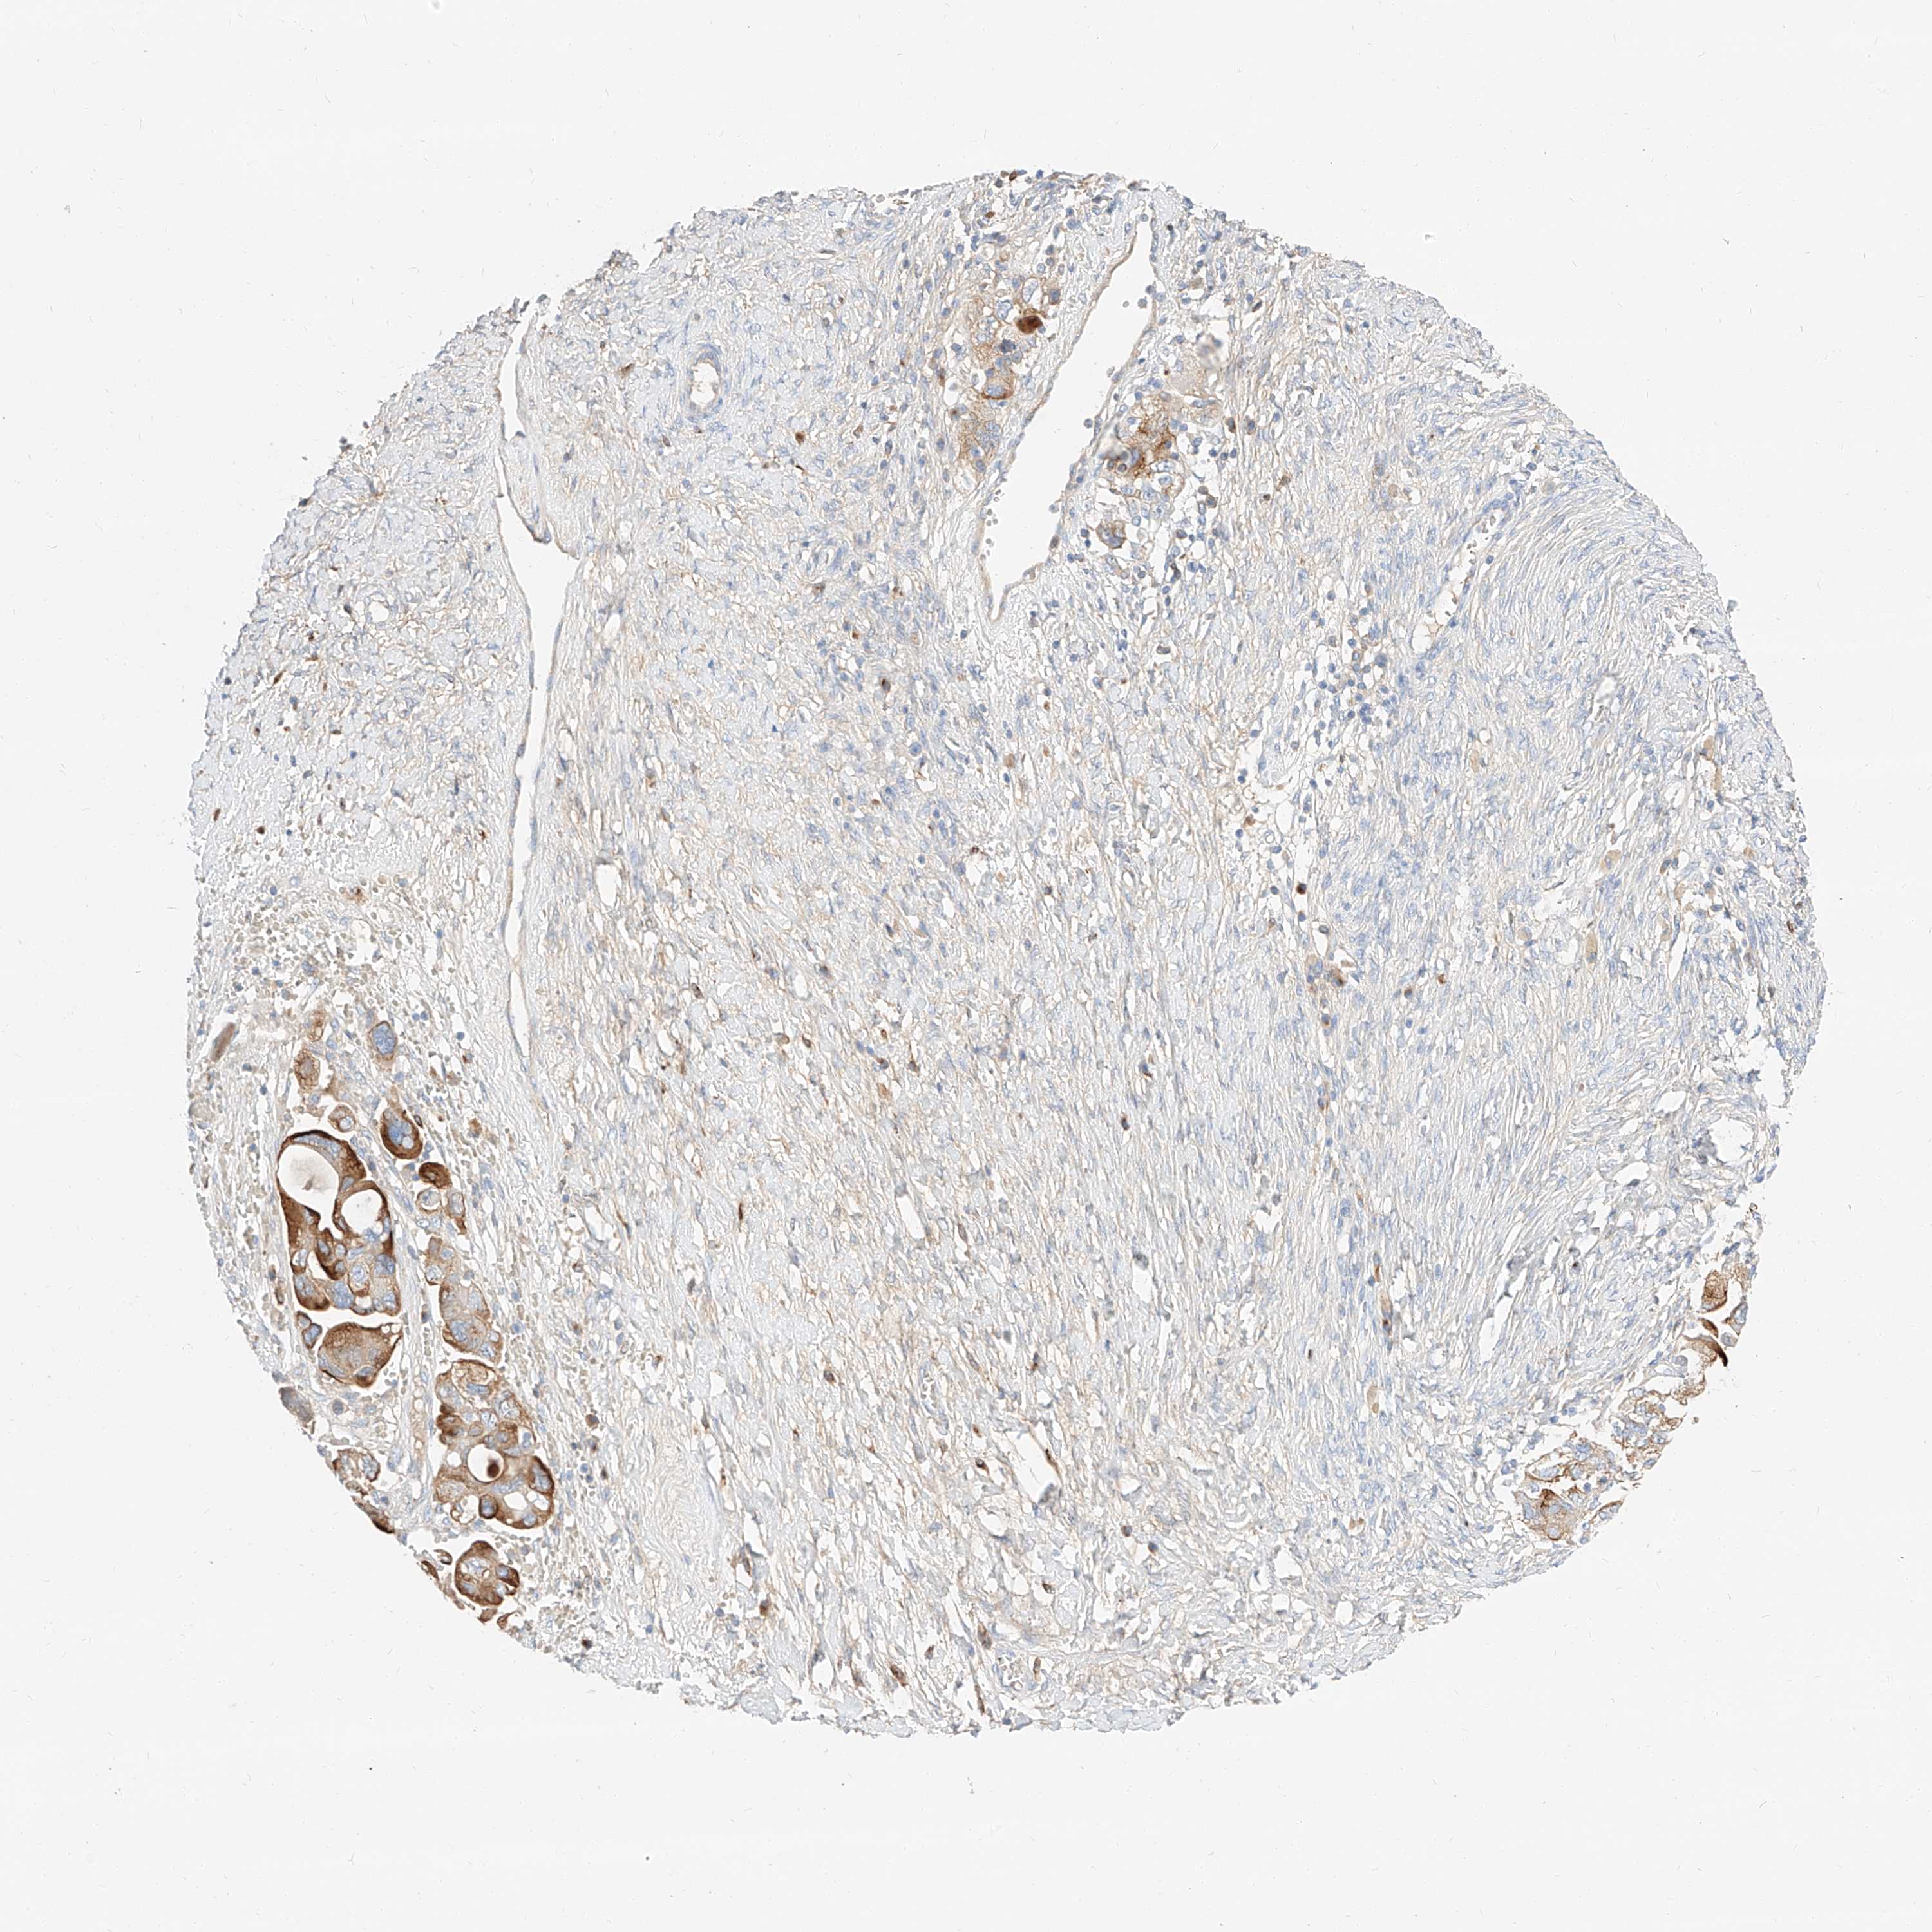

OVARIAN CANCER - Protein expressioni

A mouse-over function shows sample information and annotation data. Click on an image to view it in a full screen mode. Samples can be filtered based on level of antibody staining by selecting one or several of the following categories: high, medium, low and not detected. The assay and annotation is described here.

Note that samples used for immunohistochemistry by the Human Protein Atlas do not correspond to samples in the TCGA dataset.

Antibody stainingi

Antibody staining in the annotated cell types in the current human tissue is reported as not detected, low, medium, or high, based on conventional immunohistochemistry profiling in selected tissues. This score is based on the combination of the staining intensity and fraction of stained cells.

Each image is clickable and will lead to virtual microscopy that enables deeper exploration of all samples and also displays staining intensity scores, fraction scores and subcellular localization as well as patient and tissue information for each sample.

Antibody HPA029712

Antibody HPA029713

Staining

High

Medium

Low

Not detected

Intensity

Strong

Moderate

Weak

Negative

Quantity

>75%

75%-25%

<25%

None

Location

Nuclear

Cytoplasmic/membranous

Cytoplasmic/membranous,nuclear

Cystadenocarcinoma, serous, NOS

Carcinoma, endometroid

Cystadenocarcinoma, mucinous, NOS

Carcinoma, NOS